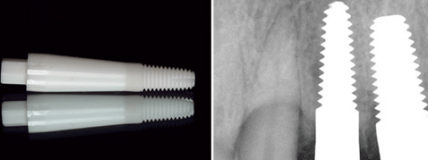

Zirkoniumdioxid Keramikimplantate

ZrO2-Keramikimplantate - Humanhistologische Aspekte eines innovativen Implantatwerkstoffes

Jahr 2009, Ausgabe 02, Seite 26 Autoren: Dr. Thomas Arzt MOM/Bad Sobernheim, Prof. Dr. Dr. Hans-Albert Merten/Hannover, Prof. Dr. Dipl.-Chem. Alfred Patyk/Göttingen